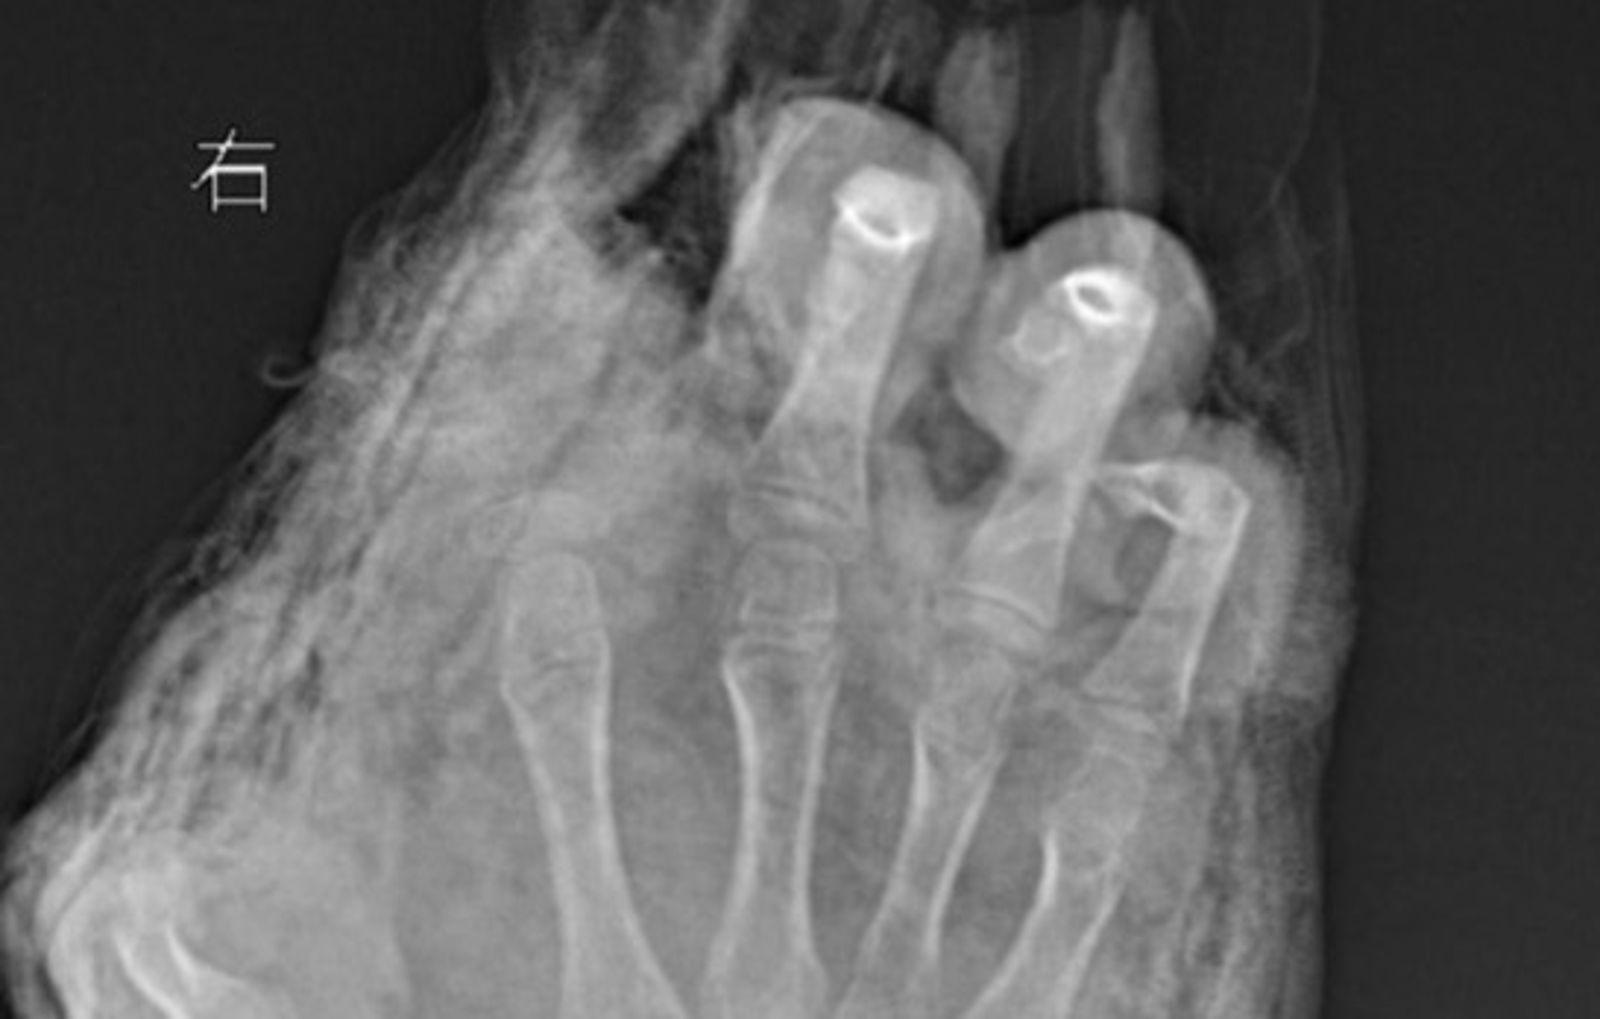

對此,武漢醫院小兒創傷及矯形中心副主任醫師徐劍表坦言,「孩子來院時,傷得觸目驚心」,表示男童右手虎口處裂傷至手腕處,右手食指完全離斷,大拇指前段1/2處被炸斷,中指遠端軟組織缺損,無名指和小拇指指腹炸傷嚴重。

醫師表示,由於男童的手掌與手指被炸傷較為嚴重,離斷的食指因血管與肌腱撕裂嚴重,無法再植,目前還要繼續觀察傷情,擇期進行二次清創及修復手術,「儘管孩子目前沒有生命危險,但這隻手未來可能會在功能、外形等方面有所影響。」